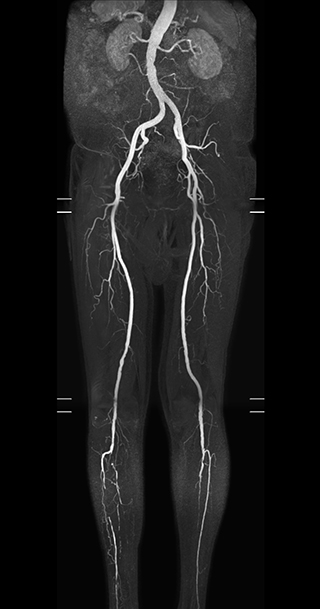

“In our peripheral MRA run-off studies with Ambition we realize key benefits, including outstanding image quality and significantly reduced breath-hold and scan times, which not only benefit the patient, but also provide the opportunity to add sequences that could aid in diagnosis,” Dr. Peña says.

“Before we had Ingenia Ambition, our CE-MRA run-off studies would first acquire a dynamic pre-contrast scan with 20-25-second breath-holds, then inject the contrast, do another acquisition and then subtract the two,” says Avila. “Now, mDIXON XD allows us to complete the study in just one single pass – without need for a pre-exam – which eliminates subtraction artifacts and almost halves the scan time. In addition, mDIXON provides much better background suppression, which really improves vesselto-background contrast. And, thanks to Compressed SENSE, the single breath-hold is not long and we improve image resolution.”

The subtractionless peripheral MR angiography shows improved vessel-to-background contrast and high resolution. Ingenia Ambition 1.5T.

| Station | Ingenia Ambition |

| Pelvis | Voxels 1.3 x 1.3 x 3.2 mm, FOV 430 mm, 125 slices |

| Upper legs | Voxels 1.3 x 1.3 x 3.2 mm, FOV 430 mm, 125 slices |

| Lower legs | Voxels 1.0 x 0.82 x 2.0 mm, FOV 430 mm, 125 slices |

The time saved by Compressed SENSE and mDIXON XD is sometimes used to include additional sequences. An example are peripheral MRA studies, in which Compressed SENSE and mDIXON XD help achieve a 5- to 10-minute reduction in scanning time. This brings the total time down, from the 45 minutes needed with their previous system to about 30 to 35 minutes on Ingenia Ambition, thus providing ample time to include additional sequences.

“These scans are so fast now that we have been able to add a non-contrast MRA sequence within the same timeslot. We compare the respective image quality with the goal to determine whether the non-contrast sequence could be an alternative for patients who can’t tolerate gadolinium contrast agents due to poor kidney function,” says Avila. “We find the image quality of the non-contrast sequence so good that we can now also offer peripheral MRA to these patients whom we had been unable to serve before Ambition, so that has been great.”